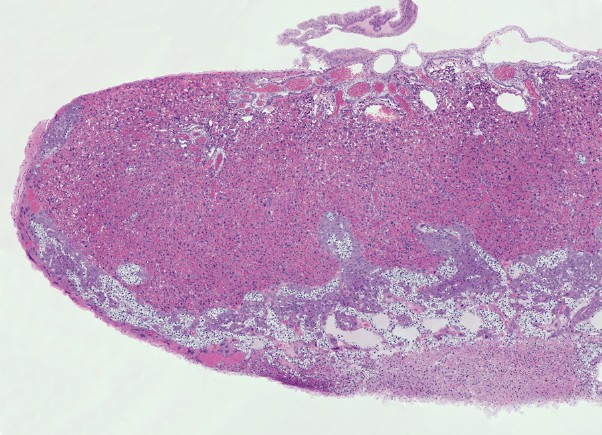

Overzicht opname placenta met zoombaar beeld.

Onderstaande opname geeft een indruk van de placenta. In het beeld hiernaast kan tot op celniveau worden ingezoomed. Ook de diverse lagen zijn te bekijken.

De muis heeft een hemochoriale placenta waarbij maternaal bloed in contact staat met foetaal chorion via een labyrintische laag (mensen hebben een vergelijkbaar type placentatie). De placenta bestaat uit maternale en embryonale lagen. De van het moederdier afkomstige laag is de decidua, die zich ontwikkelt uit het endometrium. De decidua bestaat uit twee delen: de decidua basalis en de decidua capsularis. De basalis heeft een rijk vasculair netwerk en bestaat uit losjes aanhangende onregelmatige grote vacuolate cellen met verschillend gevormde kernen van verschillende grootte.

De decidua wordt van de embryonale labyrintische zone gescheiden door de junctionele zone. De junctionele zone bevat maternale bloedvaten (veneuze drainage), trofoblastreuscellen en spongiotrofoblastcellen. Trofoblastcellen zijn over het algemeen erg groot met bizar gevormde of meervoudige kernen. Reusceltrofoblasten zijn, zoals hun naam al zegt, erg groot - tot 100 µm in diameter en bevinden zich het dichtst bij de decidua. Spongiotrofoblasten zijn fagocytisch[6] en kunnen gefagocytiseerde erytrocyten bevatten en bevinden zich dichter bij de labyrintische zone. De labyrintische zone bestaat uit nauw tegenover elkaar liggende foetale en maternale bloedkanalen. De foetale bloedkanalen zijn bekleed met dunne endotheelcellen en bevatten grote onrijpe gekerfde rode bloedcellen, terwijl de maternale bloedkanalen bekleed zijn met grote labyrintische trofoblastcellen.